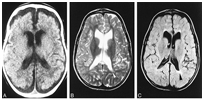

메틸말론산증이 있으면 신생아기부터 수유 후 구토와 식욕 저하를 보이며, 발달 지연과 성장 장애를 보입니다. 진단이 늦으면 의식이 없어지며, 탈수 현상이 심해지고 혈액이 산성화됩니다. 혈소판이 감소하여 출혈이 나타날 수 있으며, 백혈구가 감소하여 세균 감염에 노출됩니다. 치료하지 않으면 뇌 손상으로 인해 지능 저하, 경련이 나타날 수 있고, 사망에 이를 수도 있습니다. 신생아 시기에 진단되지 않은 채 정신 지체, 발달 지연 등이 나타나 영아기 이후에 진단되는 경우도 있습니다.

혈액의 아미노산과 소변을 이용하여 유기산을 분석합니다. 소변에서 메틸말로닌산의 배설량이 증가합니다. 또한 케톤산혈증, 대사성산증, 백혈구감소증, 혈소판감소증, 고암모니아혈증, 저혈당증 등의 소견을 보입니다. 비타민 B12에 대한 반응을 보이는지 확인하는 검사를 진행합니다. 분자유전학적 검사를 통해 methylmalonyl CoA mutase와 비타민 B12 조효소의 유전자에서 돌연변이를 발견할 수 있습니다.